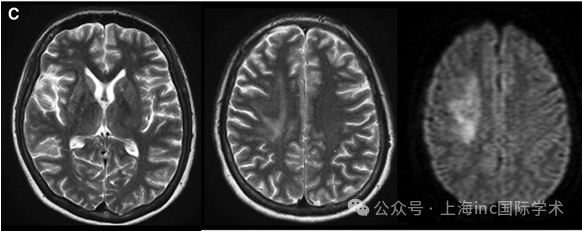

C,术前 T2 加权磁共振图像(左和中)和弥散加权图像(右)显示右侧放射冠状动脉脑梗死。